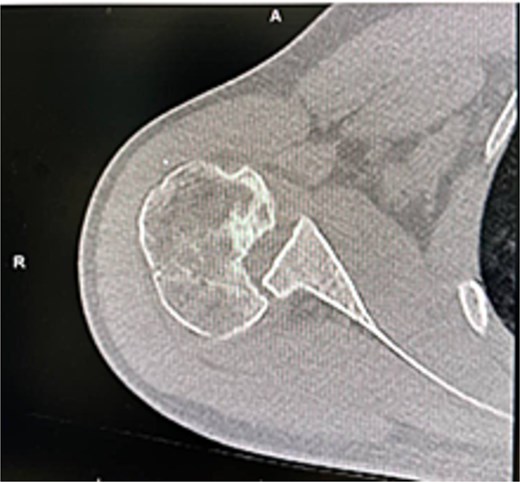

X-rays and CT confirmed missed locked posterior dislocation with healed comminuted fracture and large reverse Hill-Sachs lesion. MRI revealed posterior shoulder dislocation, reverse Hill-Sach’s lesion (Fig. 2) around 2.5 cm in diameter and 1.7 cm in depth, posterior labral tear, and secondary avascular necrosis.

He was counseled for open reduction and modified McLaughlin procedure. Through a deltopectoral approach, open reduction was achieved, and subscapularis with lesser tuberosity was transferred to the defect and fixed with a partially threaded screw. Postoperative X-rays showed satisfactory reduction (Fig. 3). He was discharged the next day in an external rotation brace.